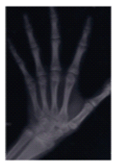

Female patient 13 years and 9 months old. Carpal radiography was performed to know in what stage of growth she was in order to decide the treatment plan (Figure 5). The patient was in the 5th stage of skeletal maturation so it was decided to place twin blocks. She was in the time limit for this technique. But in the eventuality of leaving her for surgery, it was preferred to try this device.